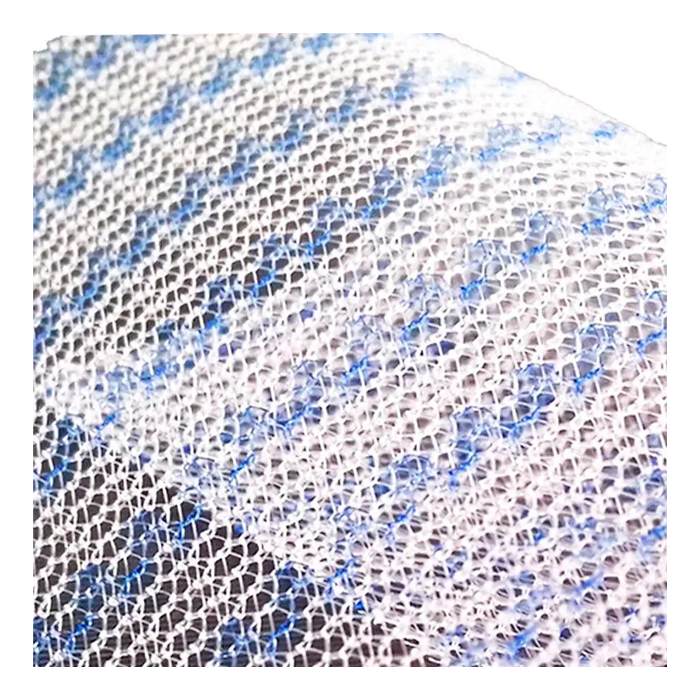

Полипропиленовая хирургическая сетка ЭСФИЛ тяжелый от компании «Линтекс» — это современный высокотехнологичный имплантат, предназначенный для надежного и долговечного укрепления тканей в ходе сложных реконструктивных операций. Изделие специально разработано для ситуаций, требующих повышенной механической прочности и стабильности.

Сетка ЭСФИЛ тяжелый обладает увеличенной плотностью и массой, что обеспечивает исключительную прочность на разрыв и минимальную послеоперационную деформацию. Это делает её оптимальным выбором для пластики обширных и сложных дефектов, где критически важна надежная и постоянная поддержка.

- Высокая механическая прочность: Увеличенная плотность полипропиленового монофиламента гарантирует устойчивость к нагрузкам и предотвращает растяжение имплантата со временем.

- Оптимальная интеграция с тканями: Структура сетки способствует активному прорастанию соединительной ткани (фиброзной инкорпорации), что создает единый прочный анатомический комплекс.

| Материал | Полипропилен (монолитная монофиламентная нить) |

| Тип плетения | Трикотажное |

После имплантации пористая структура сетки заполняется фибробластами и коллагеновыми волокнами организма пациента. Это приводит к прочному сращению (инкорпорации) имплантата с собственными тканями, создавая единый укрепляющий каркас.